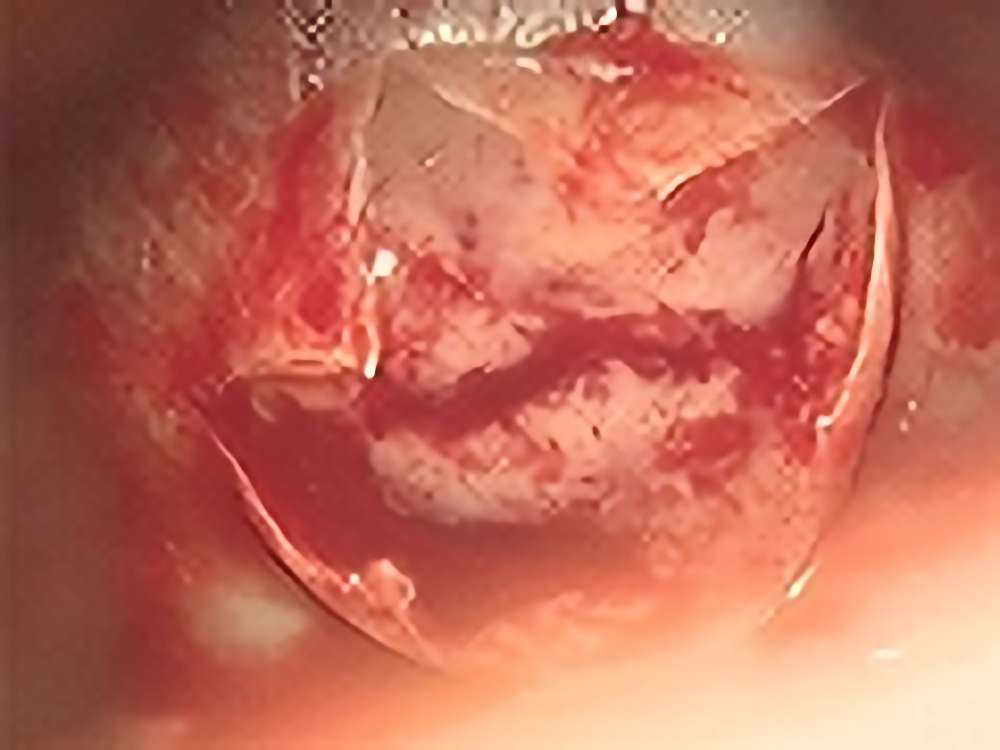

頭頂葉海綿状血管腫

No.’13_169 手術前1

No.’13_169 摘出 前

No.’13_169 摘出 後